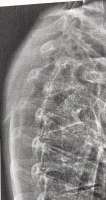

L4-L5 задняя протрузия диска

L5-S1 - высыхание диска, грыжа 7мм, стеноз позвоночного канала

Mild degenerative disc desiccation. Mild disc space

narrowing. 7 mm broad-based extruded herniation, thecal

sac compression, bilateral S1 root indentation more on the

left is noted. There is associating bilateral mild

foraminal stenosis. No central spinal canal stenosis.

Posterior central extruded herniation and bilateral

S1 root indentation more on the left.

Сделал МРТ (не в РФ, поэтому заключение частично на англ) после того, как пару месяцев спина болела - все хуево? Больно нагибаться, тяжелое не поднимаю.

Бегаю и на веле катаюсь, плаваю без проблем.

В ноги не отдает, ссу и сру нормально.

Нерв правда чувствуется на большом пальце.

Кор слабый и ягодицы тоже. При этом не жиробас.

Под операцию не хочется, врач прописал физиотерапию.

Реально эту хуйню побороть вообще?